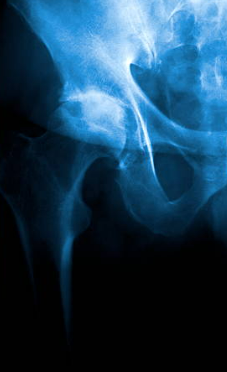

Une radiographie de bassin et de la hanche douloureuse permettront de faire le diagnostic

Radiographie

Une radiographie permettra de mettre en evidence un pincement de l'articulation, des géodes, des ostéophytes